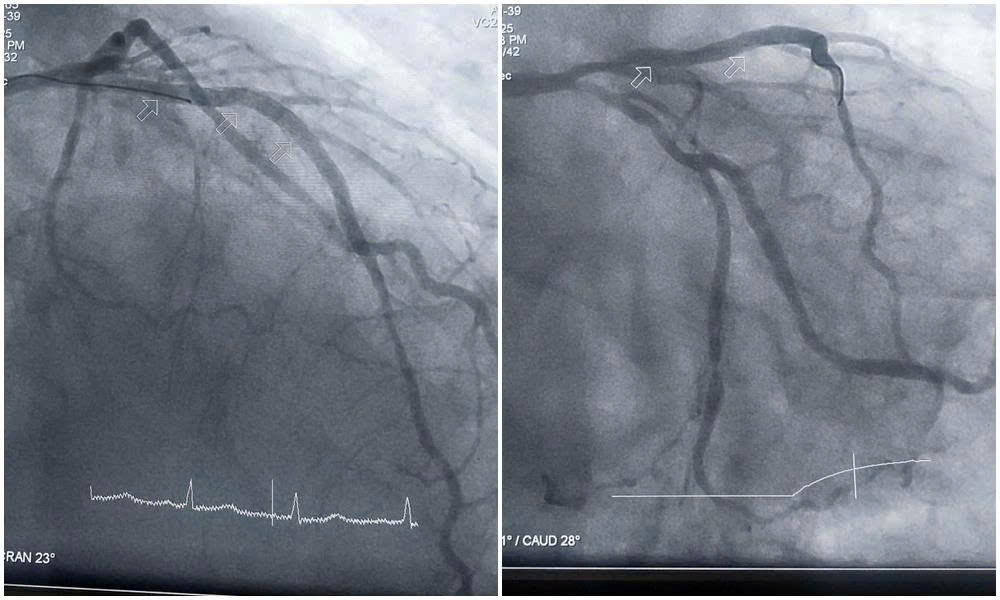

Với sự đồng thuận của gia đình, người bệnh lập tức được chuyển đến phòng can thiệp trong tình trạng huyết động không ổn định, chức năng tim suy giảm rõ rệt, đòi hỏi phải xử trí khẩn trương và chính xác. Kết quả chụp mạch vành cho thấy mức độ tổn thương nặng cả ba thân động mạch vành. Động mạch liên thất trước hẹp tới 90–99%, gần như tắc hoàn toàn; động mạch mũ và động mạch vành phải hẹp 80–90%, thành các mạch vôi hóa nhiều.

Hình ảnh tổn thương nặng 3 thân động mạch vành